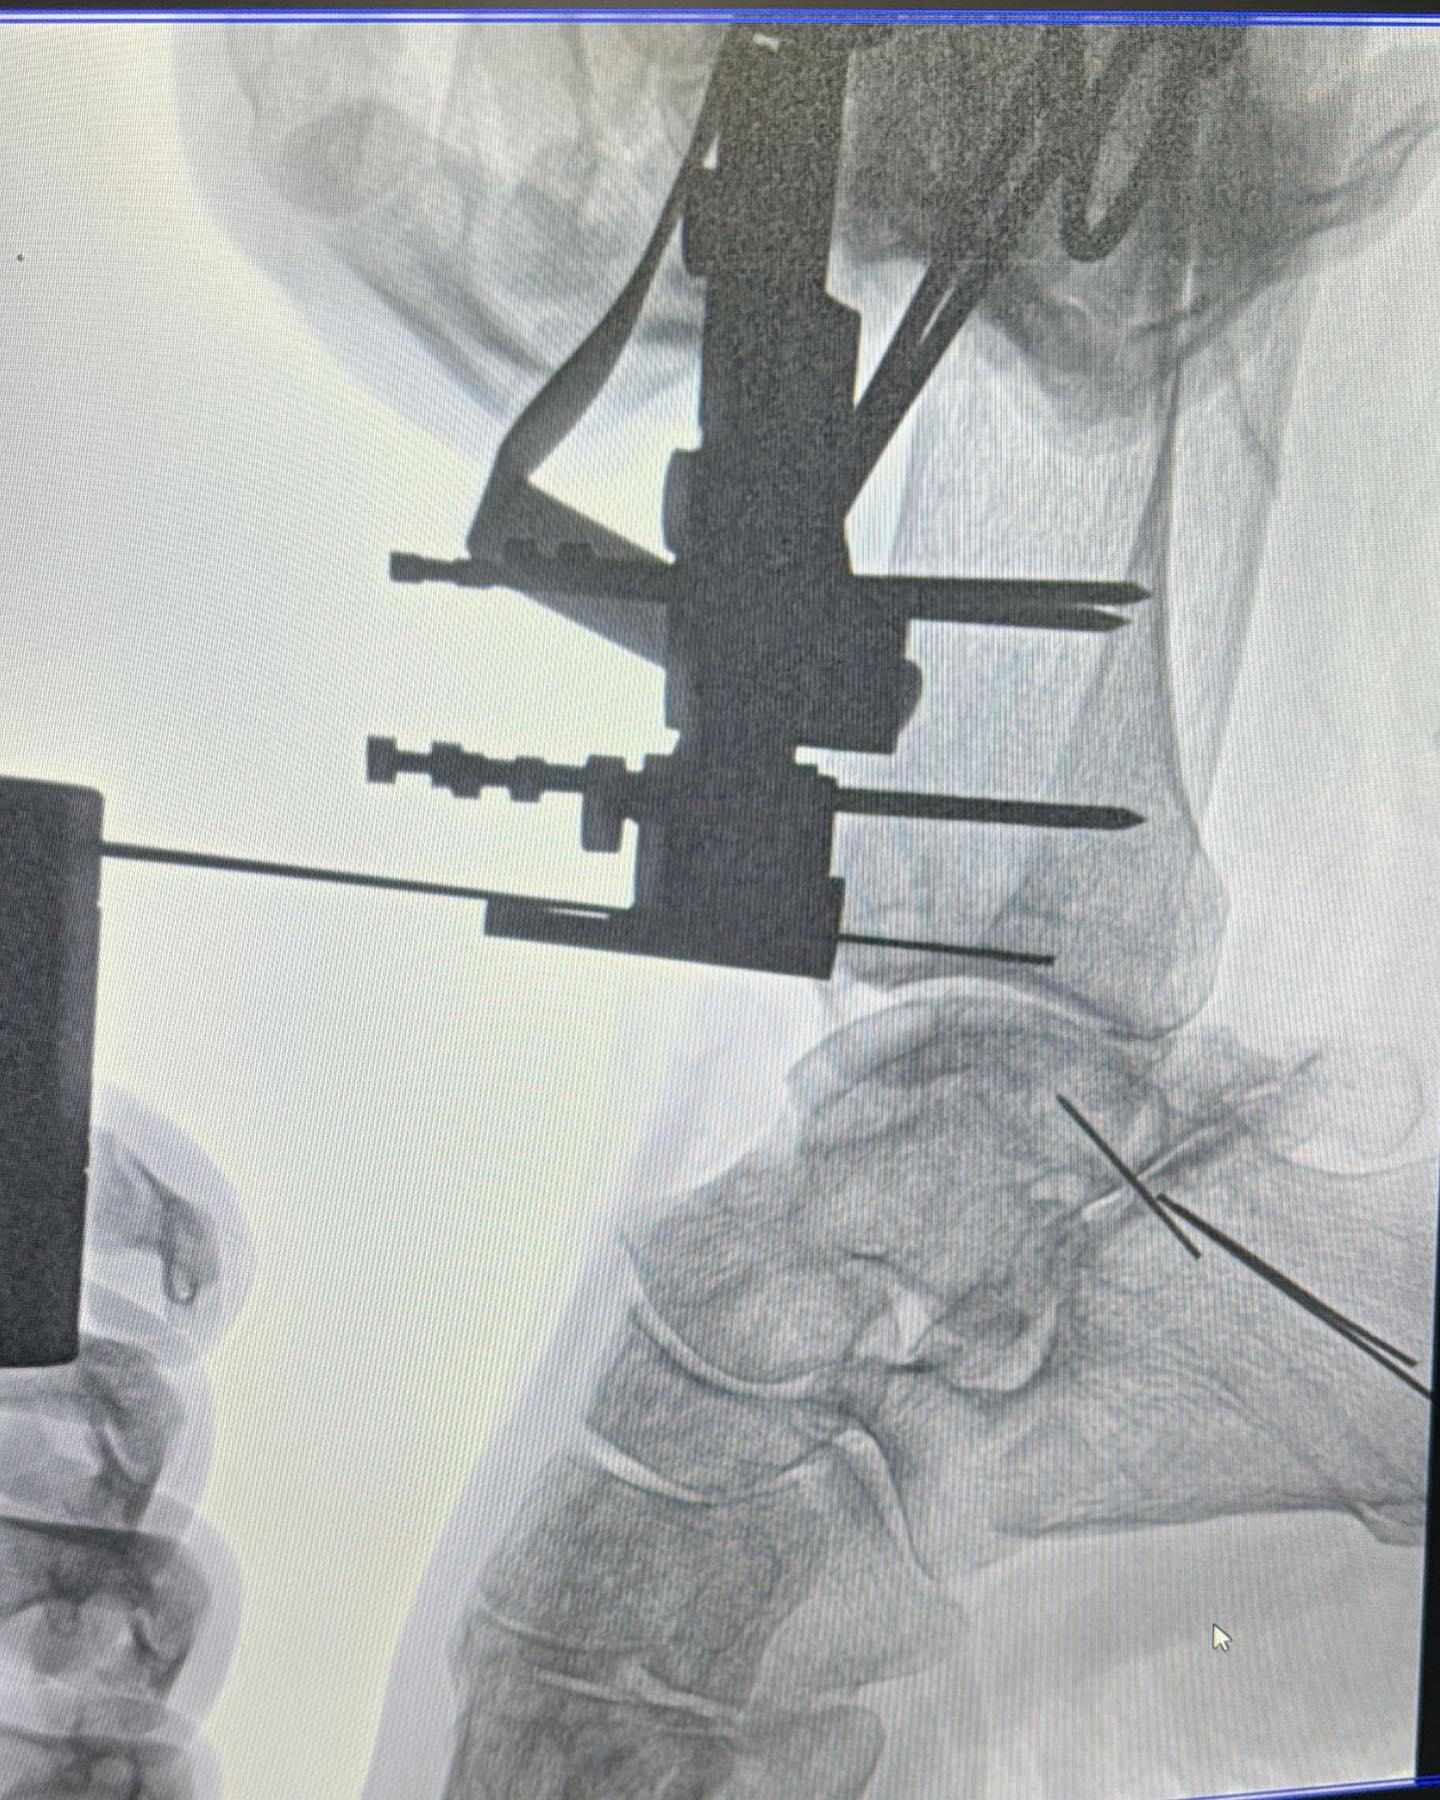

Este procedimiento quirúrgico consiste en sustituir la articulación dañada por una prótesis compuesta de metal y plástico, diseñada para restaurar la movilidad y aliviar el dolor.